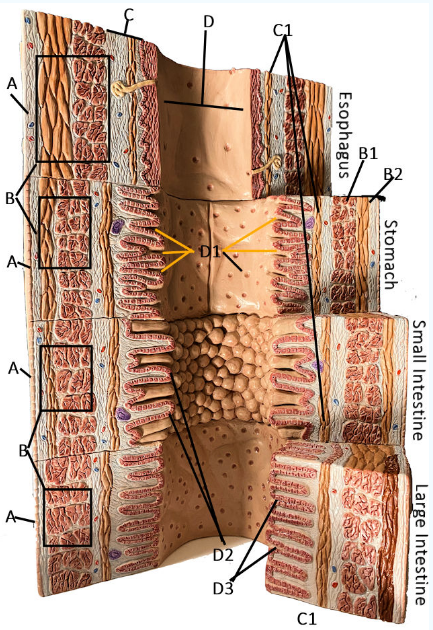

A

Serosa

B Esophagus

Muscularis externa: skeletal, skeletal/smooth, and smooth, circular and longitudinal

B Stomach

Oblique, circular, and longitudinal smooth muscle

B Small intestine

circular and longitudinal smooth muscle

B large intestine

circular and longitudinal smooth muscle

C

Submucosa: areolar and dense connective tissue

D

Lumen

D1

Gastric glands/pits

D2

Villi of small intestine

D3

Intestinal crypts of large intestine